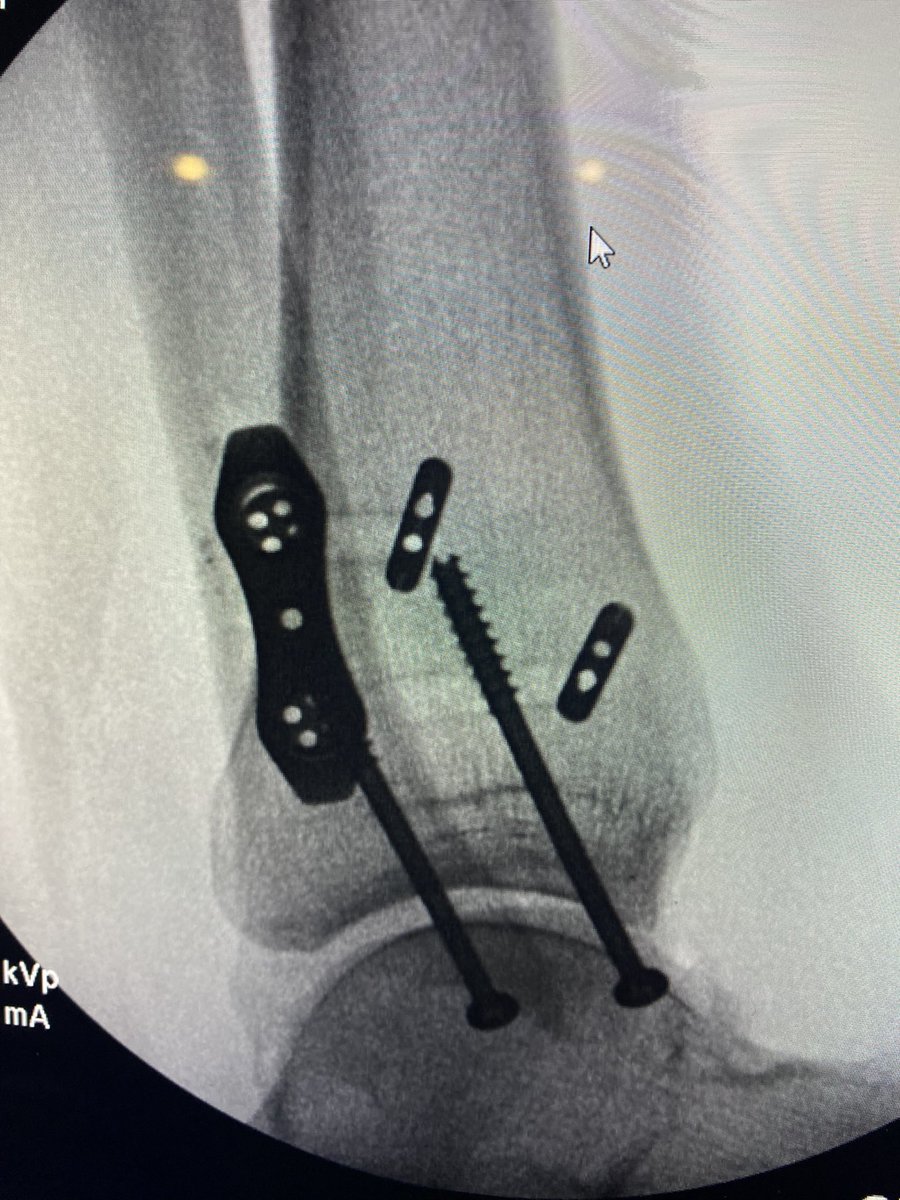

Similar case to @generalorthomd presented yesterday. Healthy 46 yo found some ice. Plan was to fix medial, and stress intra-op. @InvictaOrtho @BostonFootAnkle @pmangoneMD @traumaticum @StressHoop @DrAdamBitterman @DrBhavinJadav @generalorthomd @Davembmd @davidhcmd @MilanSenMD

English